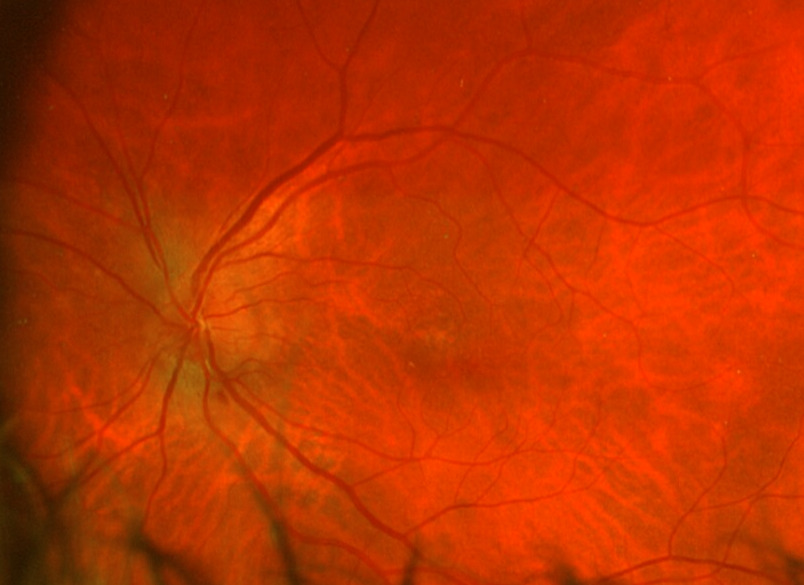

Posterior segment revealed IOL implants that were clear and centered after YAG Capsulotomy in both eyes. The optic nerve heads were both crowded with cupping of 0.10/0.10 (H/V) OU. The neuroretinal rim was intact in the right eye with no evidence of hemes, pallor, edema, or neovascularization of the disc. When observing the left eye, an inferior and inferior temporal rim hemorrhage was noted. Clinically, there was no apparent edema. There was a questionable area of swelling inferior temporal and superior temporal, but it was difficult to view. The vessels surrounding the optic nerve did not appear to be obscured and no spontaneous venous pulse was noted. The macular area was flat with even pigment and no clinically significant macular edema was present in either eye. Vessels displayed a normal AV ratio. The peripheral exam noted no holes, breaks, or tears in either eye. Finally, giant cell arteritis (GCA) symptoms of were ruled out.

On this visit, the patient’s posterior pole revealed a blurred inferior temporal neuroretinal rim in both the left and right eyes. The right eye previously had no appearance of edema in the initial visit. The discs were crowded at .10/.10 OU as noted at initial visits and no hemorrhages were seen on this examination. All other structures posteriorly were consistent with the original examination.

After additional testing was completed, and comparison of previous photos were conducted, it was determined that the patient had not only optic disc drusen, but also possible bilateral amiodarone optic neuropathy. The photos 4 months apart shows increasing pallor in the left eye and a blood vessel at 7 o’clock that did not look obscured initially but was evidently more pronounced on the follow up when comparing the initial and follow-up photos. This shows the importance of quality serial fundus photography.

Right image is original exam with inferior hemorrhage. Left image is 4-month follow-up visit. Resolution of the hemorrhage is seen, but atrophy of the disc overall should be noted. Vessel at 7 o’clock should also be noted. It appears much more pronounced than on initial visit.